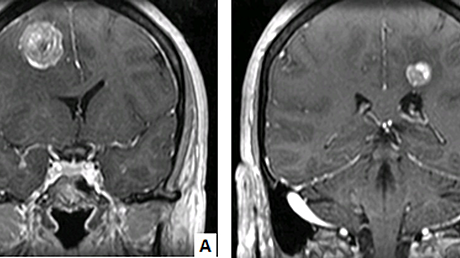

A midline vertical incision is made from S3 till few centimeters caudal to the palpable mass. The tumor mass was separated from the surrounding tissues taking healthy margins circumferentially and separating it from skin and fascia laterally and from recto-sacral fascia ventrally taking care of the rectum. The tumor was removed en-bloc as seen in Figure 3 by resecting through the body of S4 vertebrae.

However, sacral nerves were spared. Hemostasis was secured and the wound was closed in layers over a drain. The patient is symptom-free at two years follow-up.